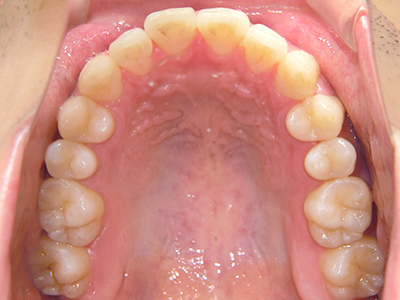

ないき歯科クリニックでは、上あごの成長不足を補い、鼻呼吸を獲得しつつ歯列を整え、将来のお口をより健康な状態にすることをゴールに定める矯正治療をおこなっています。

矯正装置を装着し、調整しながら少しずつ歯を移動させ、歯並びを整えていきます。